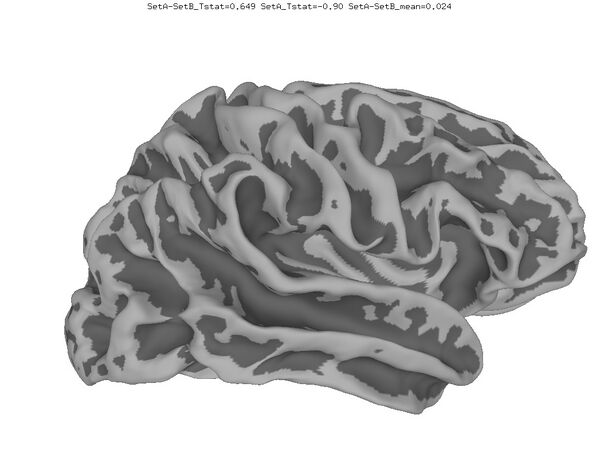

Anatomical Data

New

Old